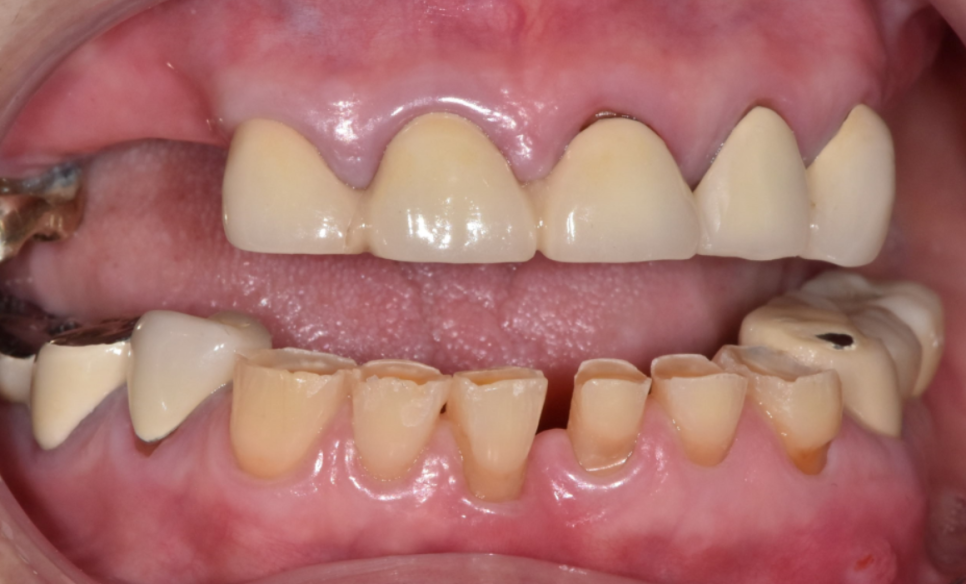

이 환자분은 오랜 시간 동안 치아가 많이 닳아,

전체적으로 치아가 낮아진 상태였습니다.

입안을 보니

앞니뿐 아니라 어금니까지 평평하게 닳아 있었고,

오른쪽 아래 임플란트 보철이

유난히 낮게 제작되어 있었습니다.